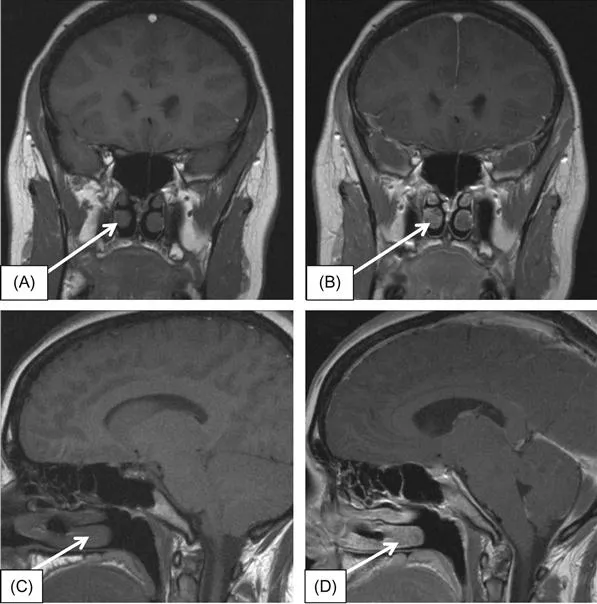

II. After distinguishing T1- and T2-weighted images, the next step is to identify the pre- and postcontrast T1-weighted images. For physicians with less familiarity with pituitary imaging, looking at the nasal conchae is an easy way to differentiate between pre- and postcontrast images. In precontrast images (Figure 1.3A and C), the nasal conchae have intensity similar to the brain gray matter (isointense); however, on postcontrast images (Figure 1.3B and D), the nasal conchae appear brighter than the gray matter (hyperintense). Note that the pachymeninges (dura mater) and falx also show conspicuous brightening after gadolinium administration. MRI contrast agents (which use a water-soluble gadolinium chelate...